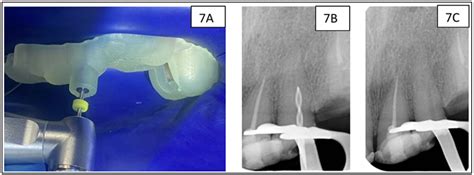

Cómo se usa los Palos de medida y anilleros, para llegar a la medida exacta.